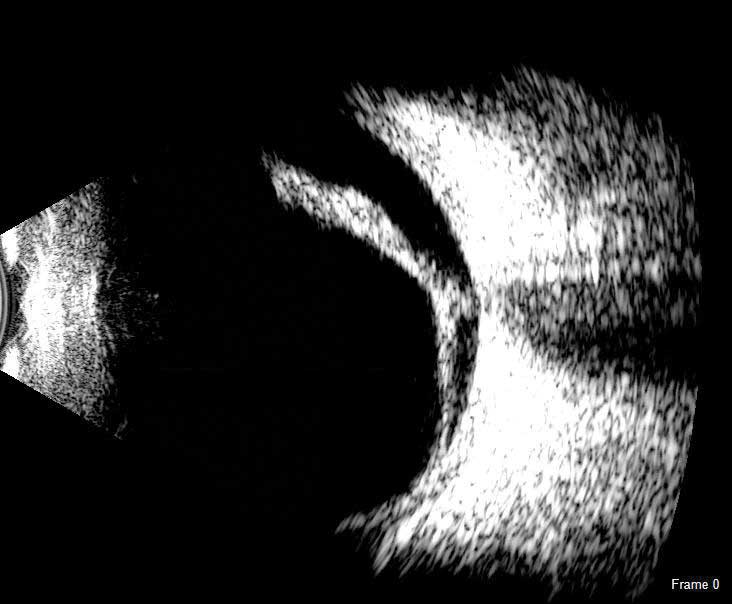

UBM

UBM незамінний при візуалізації переднього відрізка ока. Зображення з високою роздільною здатністю UBM дають можливість спостерігати структури, приховані райдужною оболонкою або помутніннями рогівки.

Програмне забезпечення Scanmate надає інструменти для вимірювання кутів, площі та довжини, а також інструмент анотації для позначення патологій. Наповнений водою одноразовий стерильний чохол Clear Scan® Probe є єдиним компонентом, який торкається ока.

UBM зонд застосовується для: Вимірювання ACA; Оцінки рогівки після LASIK; Моніторингу положення ІОЛ; Передопераційної оцінки ICL; Діагностики кіст райдужки та циліарної оболонки; Післяопераційного обстеження глаукоми.